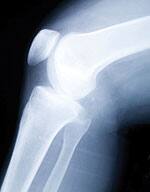

Painful joint deterioration caused by osteoarthritis ranks among the most common, debilitating conditions confronting aging individuals today. It is also rapidly on the rise, in both young and old alike due to excess body weight. An estimated 27 million Americans age 25 or older currently suffer from osteoarthritis.1 By 2030, a projected 67 million people will have doctor-diagnosed arthritis.2 A new therapy might reverse this trend. The technology is called autologous stem cell transplantation. It involves using undifferentiated cells that can develop into almost any tissue—new cartilage, tendons, ligaments, even bone—to replace damaged, arthritic joints. These cells are taken not from human embryos but from your own body! At the forefront of this research is Colorado-based regenerative medical expert Dr. Christopher Centeno. His clinical work has already yielded intriguing preliminary results—up to 75% pain reduction without surgery or side effects in scores of patients. In this article, the facets of Dr. Centeno’s new therapy are detailed. You will then learn of the FDA’s inhumane attempt to block Dr. Centeno from using this experimental therapy. In this instance, the FDA is erecting a regulatory barrier to deny patients access to their own stem cells—in all likelihood to protect drug company profits. Osteoarthritis: The Scourge of Aging IndividualsOsteoarthritis is a progressive condition for which no cure exists. Affected joints undergo gradual degradation of cartilage, the natural slippery, lubricated tissue that allows smooth movement and weight-bearing.3 As the cartilage deteriorates, friction increases, leading to severe pain and ultimate destruction of the joint.4 In one of nature’s seeming cruelties, cartilage is poorly supplied with blood, making it slow to heal. Worse, damaged cartilage will not regenerate itself under normal circumstances.5,6 Since osteoarthritis is common in previously physically active people, it can significantly impair quality of life in those who suffer from it, particularly as they age.7-9

Many modern surgical repair procedures are aimed at disrupting cartilage deeply enough to trigger a natural repair response from the bone underlying the cartilage—but the result is often incomplete and inadequate.9,10 Over the past several decades, surgeons have developed techniques for removing small “plugs” of healthy cartilage from uninvolved areas of joints and transplanting them into the damaged areas, sometimes culturing the cells first to increase their numbers.4,6 While these techniques have shown some promise, they have the disadvantages of damaging otherwise intact cartilage without adequately restoring joint function.5,9 Another challenge osteoarthritis poses for clinicians has to do with aging itself: in the case of knee replacements—one of the most common procedures—the “repair” does not last for a long time, so orthopedists paradoxically delay the first surgery for as long as possible. For this reason, all too many osteoarthritis sufferers are told to wait until the disease becomes severe enough, or they grow old enough, to warrant full-scale artificial knee replacement surgery. Until then, they must rely on pain relievers or periodic injections of anti-inflammatory steroid drugs while they get older in pain. When they finally do have the procedure performed, they face yet another lengthy period of debilitation: total knee replacement is major surgery, with patients typically advised to count on up to 6 weeks of limited activity, and 6-12 months of gradual rehabilitation to return to normal function.11 That alone explains orthopedists’ keen interest in discovering faster and simpler solutions. Personalized Therapy Using Your Own Stem CellsMost people have heard of stem cells—the powerful “precursor” cells that can differentiate, or mature, into virtually every type of tissue in the body. Early work with stem cells involved “harvesting” them from human embryos, which raises a host of ethical issues. Also of concern is the fact that embryonic stem cells, precisely because they are so versatile, carry the risk of transforming into tumor cells.12